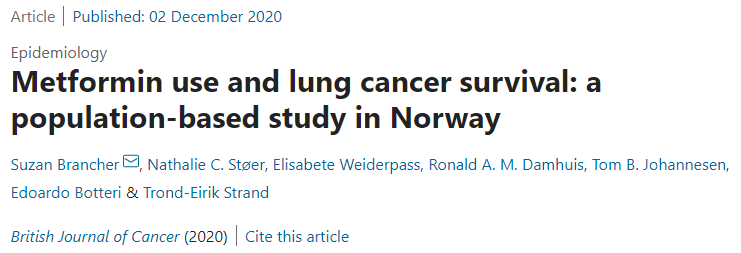

二甲双胍对肺癌生存有哪些影响?死亡风险显著降低...

二甲双胍对肺癌生存有哪些影响?死亡风险显著降低...